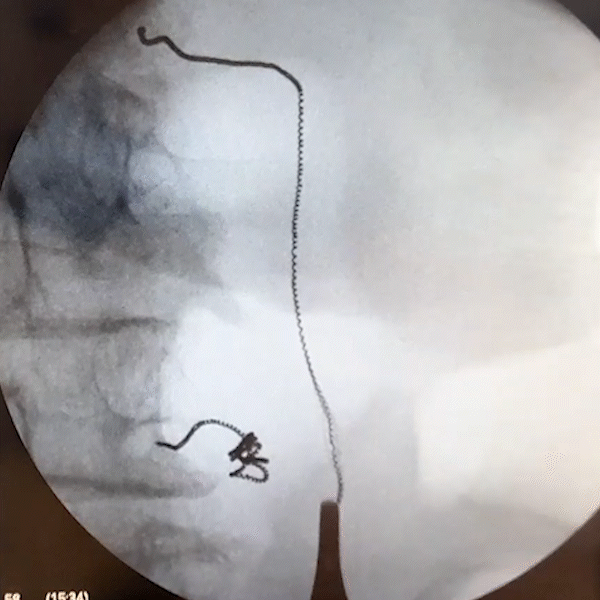

Another common neuromodulation target is the posterior tibial nerve (PTN). The Injectrode’s placement procedure allows clinicians to customize the size of each anchor (stimulating anchor, central anchor, subcutaneous collector) for each patient’s unique anatomy.

Out of plane ultrasound imaging can be used to easily identify the target nerve and allow for needle trajectory planning to minimize tissue trauma. The delivery needle is guided to the target and is angled roughly parallel to the nerve for Injectrode deployment. The Injectrode’s flexibility makes the PTN a suitable target, as the device conforms to the PTN, with the stimulating anchor capable of curving around the nerve after placement.

By creating a low-resistance path, the Injectrode is a promising approach for the future of PNS treatment.